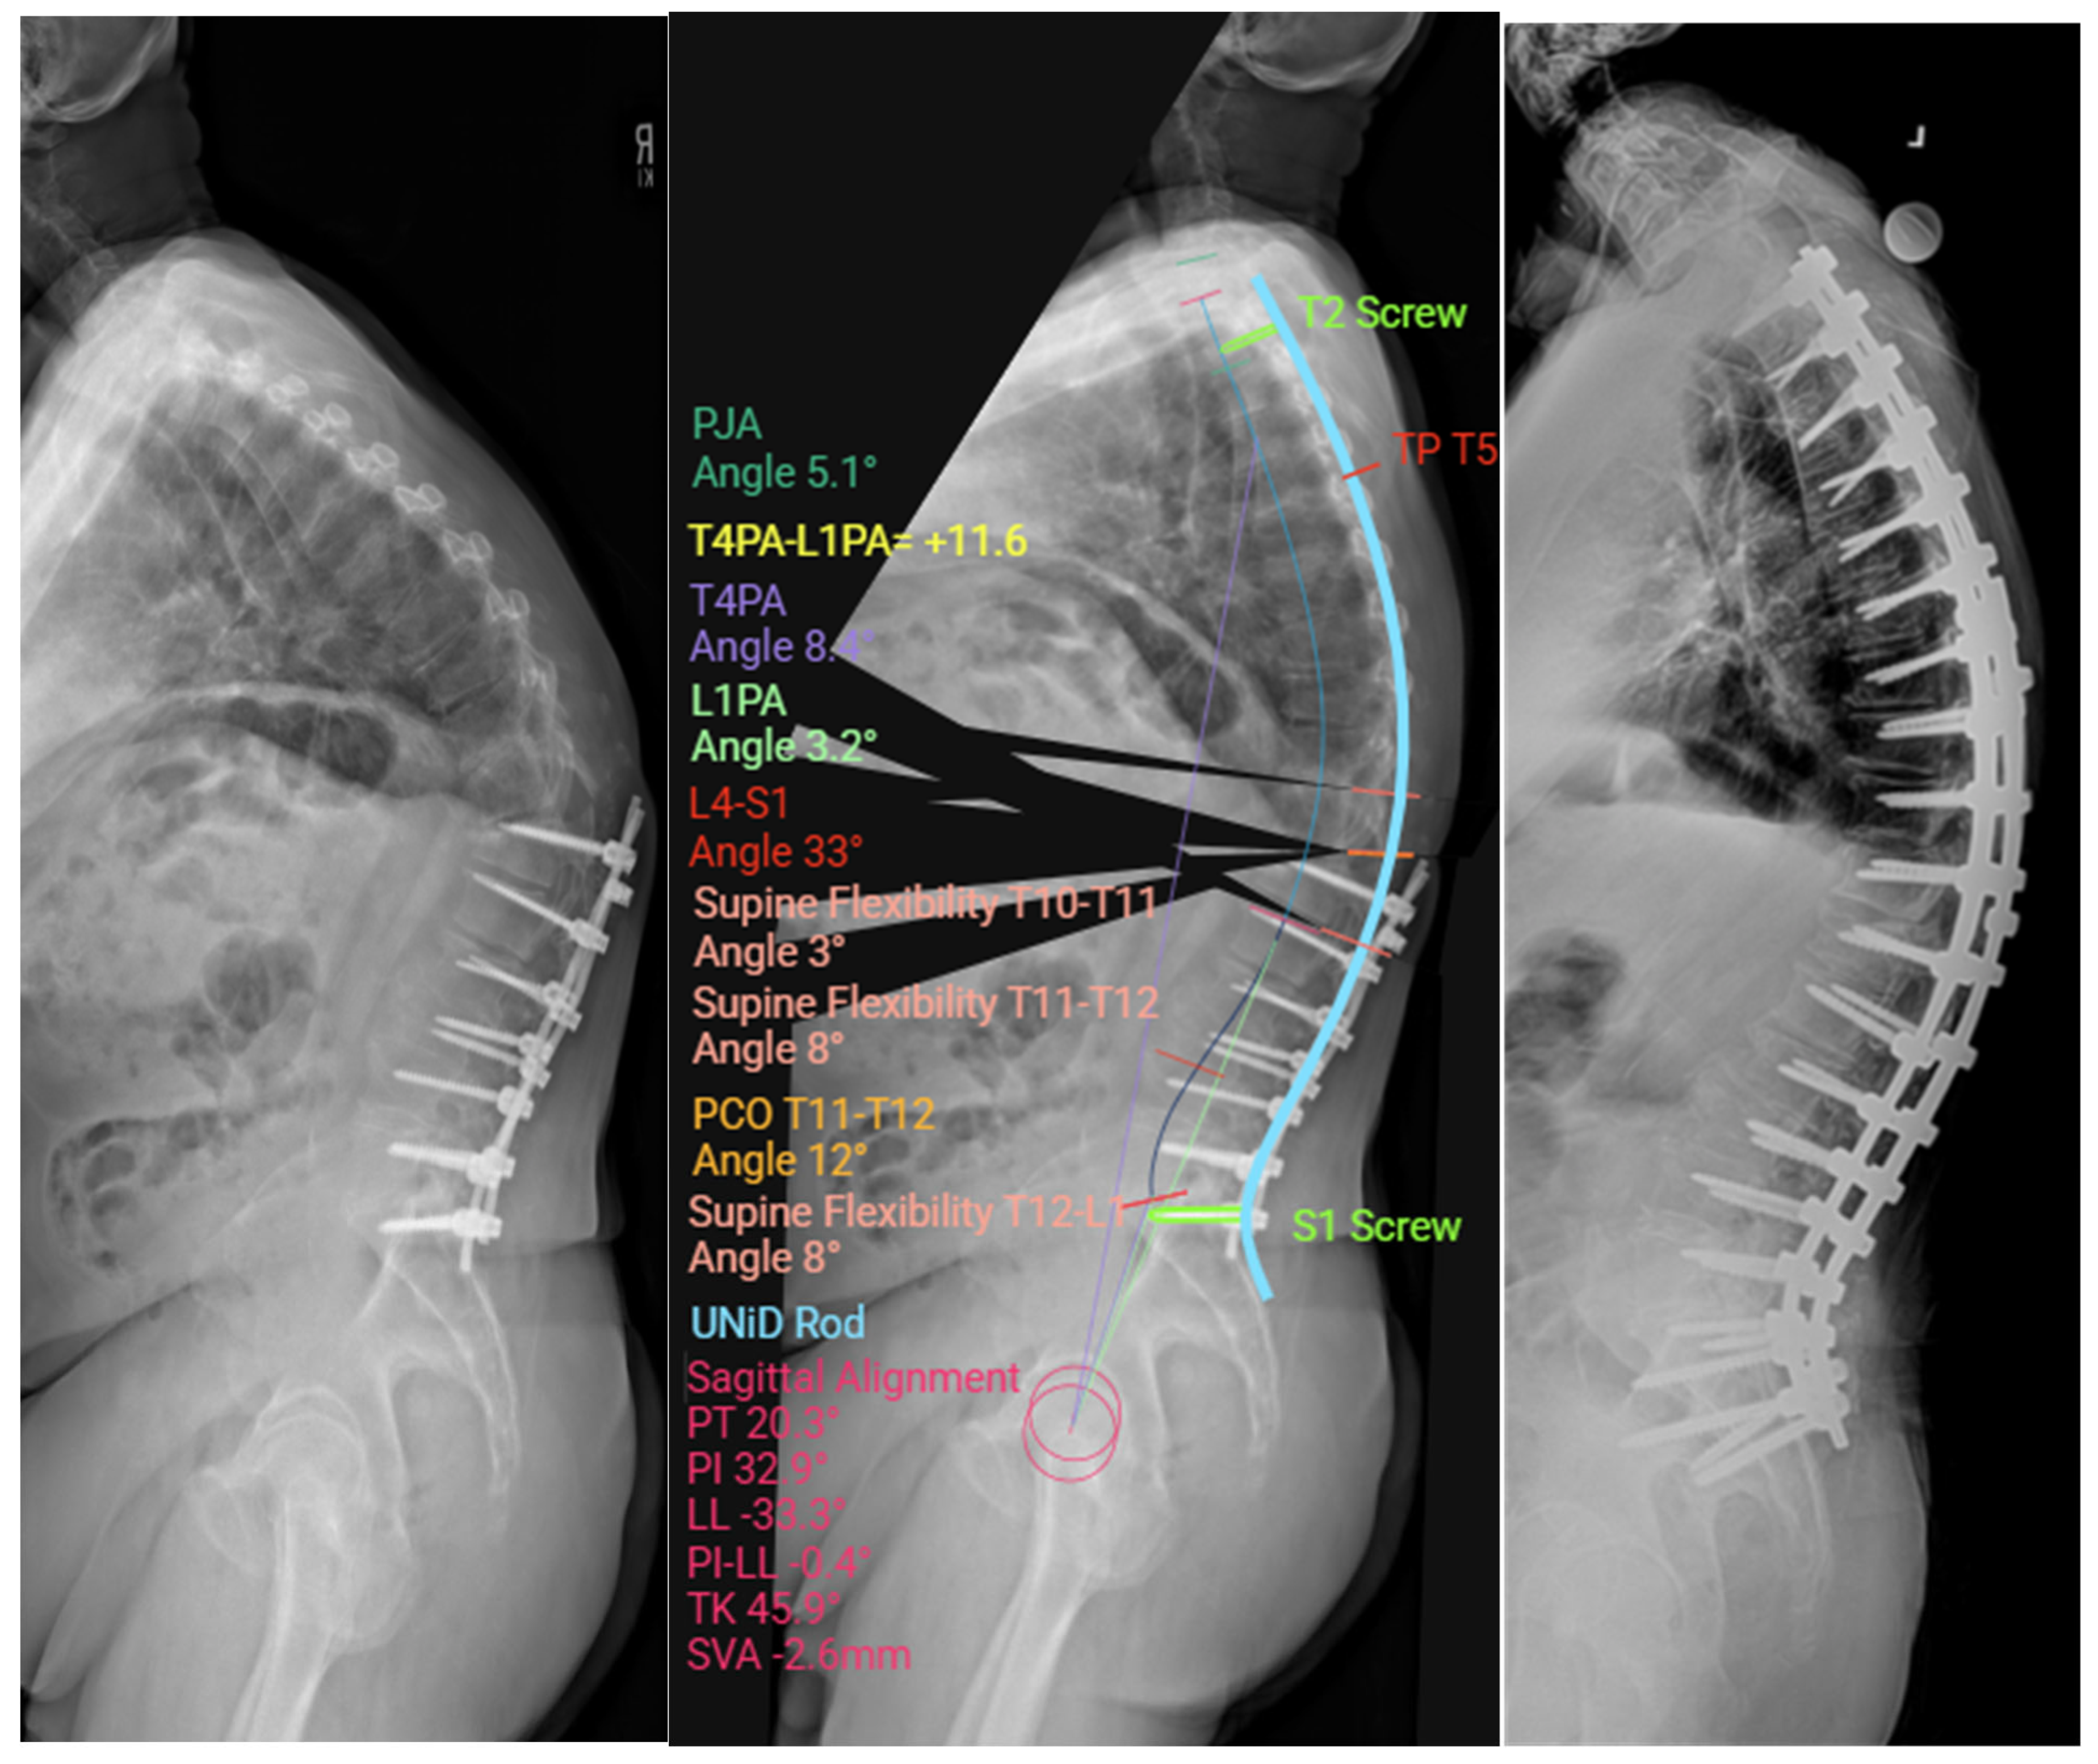

2.4. Preoperative Planning and Predictive Modeling

2.7. Custom Patient-Specific Rods